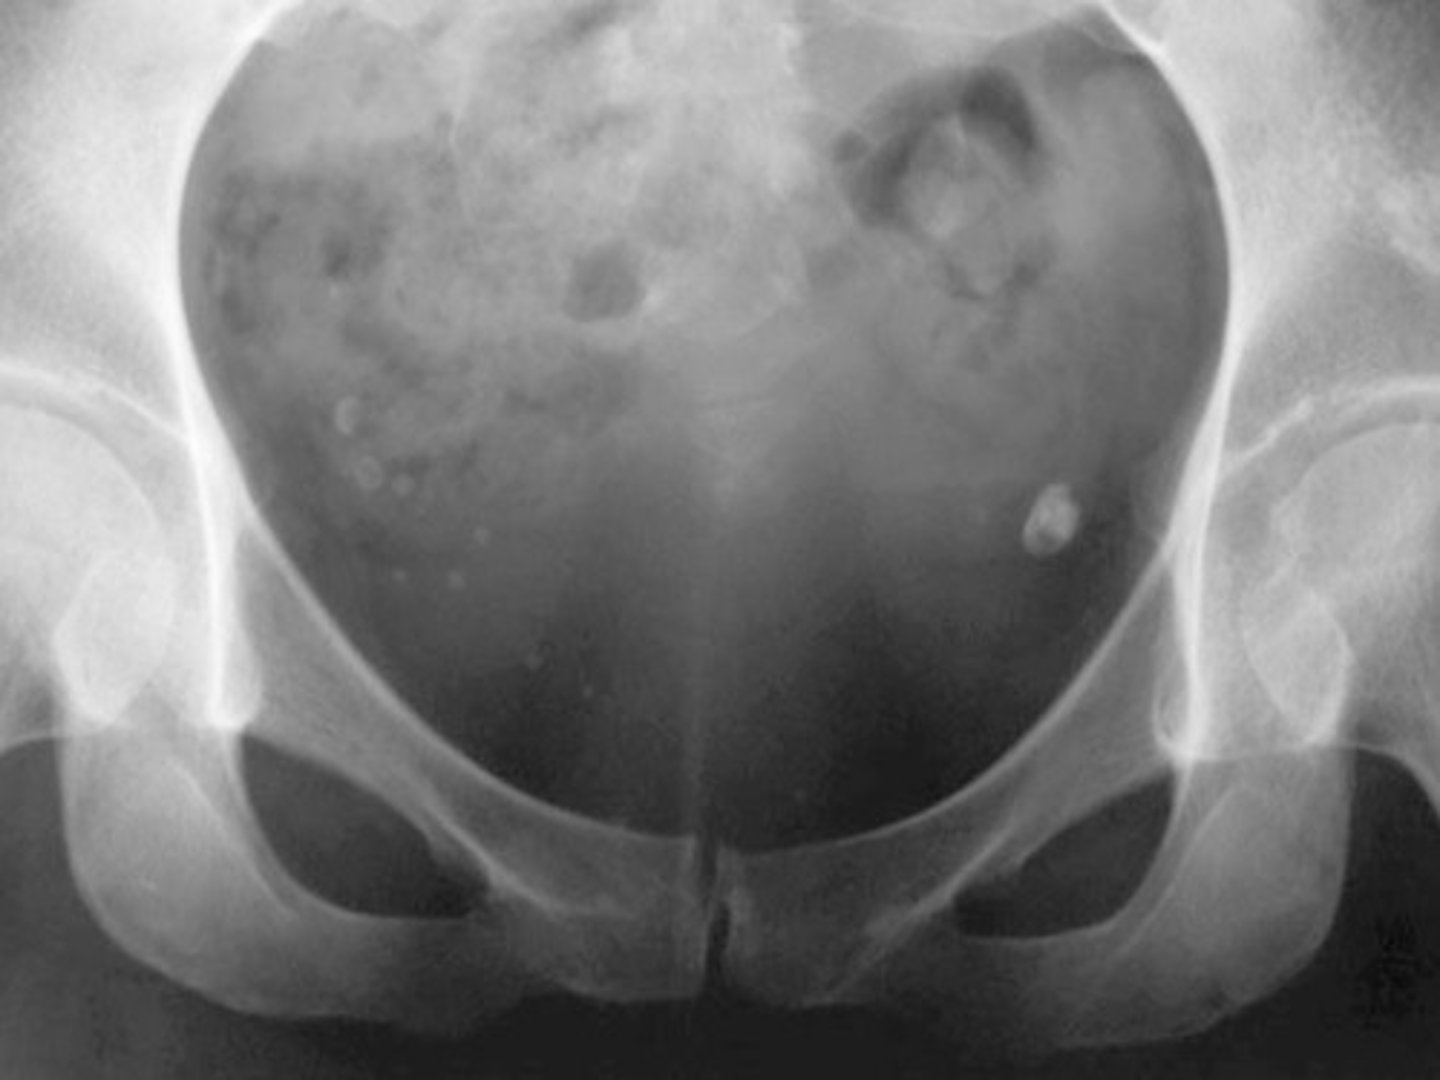

Acetabular Protrusion (aka Protrusio Acetabuli)

Intrapelvic displacement of the acetabulum and femoral head, resulting in the femoral head projecting medial to the ilioischial line

Imaging findings of Acetabular Protrusion

— Center-edge angle (Wiberg Angle) greater than 40 degrees and medialization of the medial wall of the acetabulum past the ilioischial line (Kohler's Line)

— Acetabular fossa greater than 3 mm beyond the ilioischial line in men and 6 mm in women

— Projection of the femoral head medial to the ilioischial line

Causes of Acetabular Protrusion

Primary (developmental)

Secondary (pretty much anything that soften's bones)

— Paget's

— Psoriatic arthropathy

— RA

— osteomalacia and Rickett's

— Marfan Syndrome

— Osteogenesis imperfecta

— Hemophilia